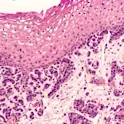

Lung cancer, photomicrograph of small cell carcinoma As the scientific landscape across the field of oncology is constantly evolving, discussion around the latest treatment options in Thoracic Oncology is vital to help align on a common approach to the treatment of lung cancer – the leading cause of cancer-related death worldwide. Prof Solange Peters and Dr Alfredo Addeo are this year’s chairs of the 4th International Lung Cancer Summit (ILCS) held in Lausanne, Switzerland. Frontiers in Oncology has an ongoing relationship with the summit and are proud to be involved in supporting a platform for sharing the latest discoveries and advances towards the treatment of lung cancer. Prof Peters is the chair of Medical Oncology in the department of oncology at Lausanne University Hospital. She is also the chair of the European Society for Medical Oncology (ESMO) Women for Oncology Committee and the youngest ever ESMO president. Dr Addeo is a consultant medical oncologist at the University Hospital of Geneva, Switzerland. He is also an active ESMO member and one of our Associate Editors in Frontiers in Oncology. Dr Addeo has been involved in leading multiple successful collections in our Thoracic Oncology section including ‘New Insights Into Targeting ALK in Patients […]